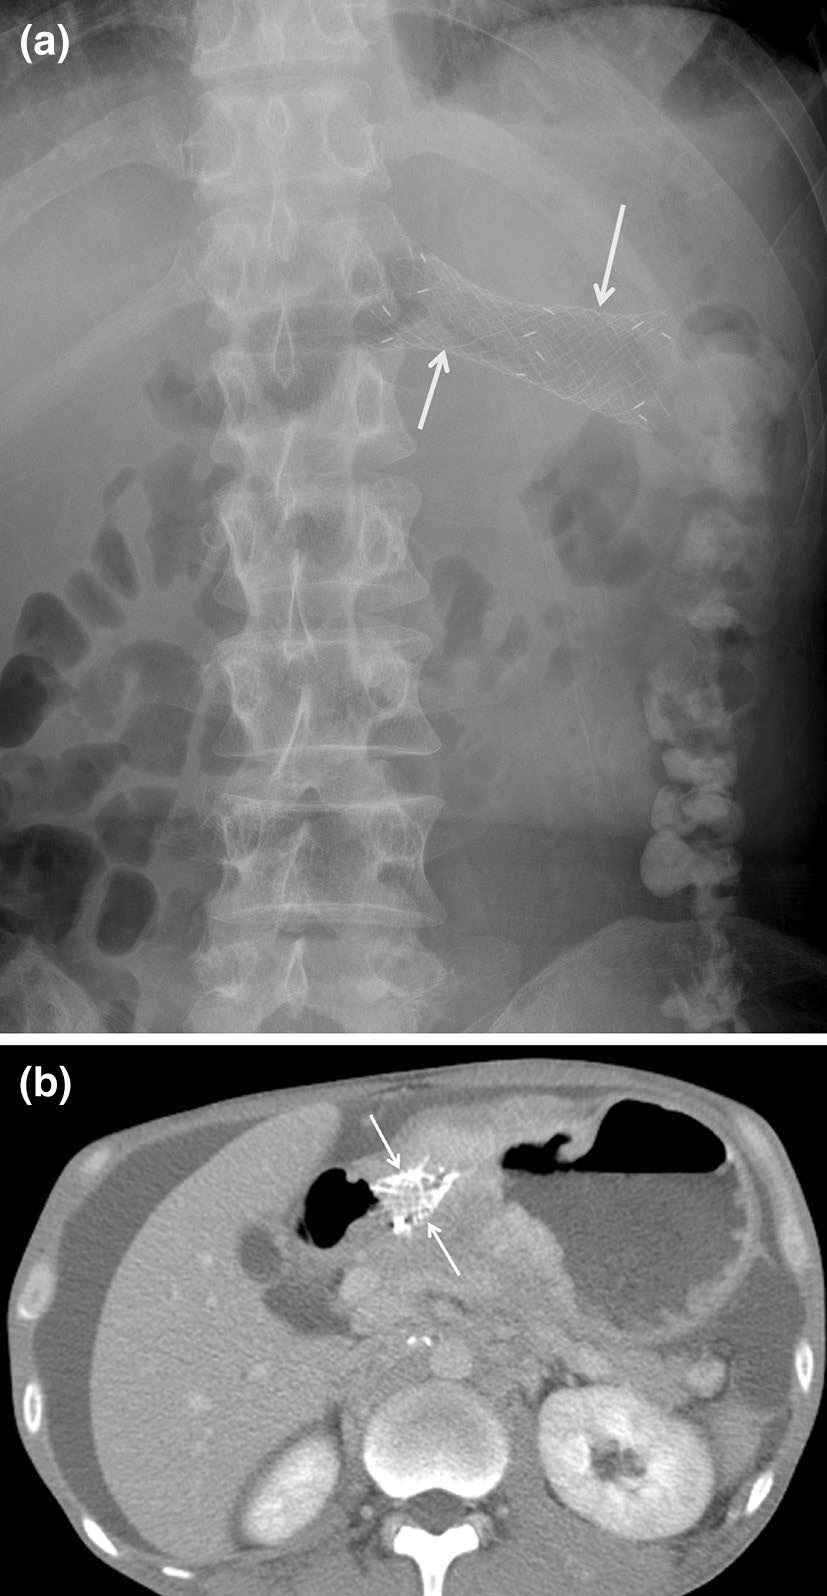

胰管和胆道支架

胰管和胆道支架由塑料或金属制成,通常用于胰管或胆管阻塞的患者。主要不良事件是迁移和支架堵塞。胰管或胆道支架发生迁移的情况占5–10%(图1)[5]。与覆膜金属支架或塑料支架相比,裸露的自膨式金属支架迁移发生率较低。